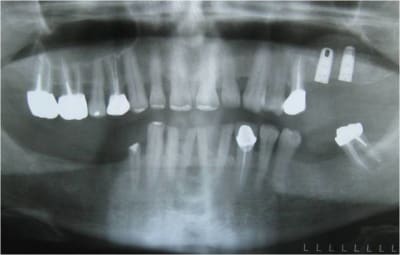

bon, comme dans le titre, une petite ROG avec pose de 3 leone (un 4.1/12 en 24, 4.1/8 en 25 et un 6.5/5 en 26)

pose de 3 cap de 1.5mm permettant de faire piquet de tente pour la rog réalisée avec du kasios et une membrane collagène AT de 22x22mm

sincèrement, j'aurais pas eu un implant court de 6.5mm planté dans à peine 3/4mm d'os, j'aurais fait un bridge entre 14 et 16...

à giantcoco, dans ton étude y figure ce genre de cas? ou c'est des implants courts totalement enfouis dans l'os?

là le cumul des risques m'a fait préférer bétonner en posant 3 implants et ce d'autant plus que j'avais largement la place

pour ce qui est de nombre d'implant je l'aurais abordé comme toi mais j'aurais plus certainement cherché a gagner de l'os au niveau du sinus (le rapport implant/couronne ne semble pas poser problème).

oui, mais t'as pas vu l'image dans le sinus?

l'orl ne veux pour l'instant pas y toucher mais j'avais son feu vert si pas de soulevé...et comme il y avait un défaut horizontal...et bien ROG...;-)

je joins les radio et scan que j'avais oublié tout à l'heure.